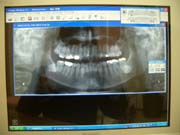

<デジタルレントゲン>

従来型のレントゲンに比べ、被曝量を大幅に軽減しております。

又、現像の際に廃液も出ないため、環境にも優しいものです。

現像までお待たせすることなく、お座りの診察台のパソコン画面で鮮明なレントゲン画像をご覧頂けます。